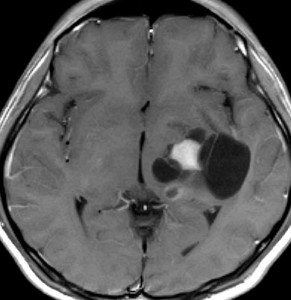

10才の時に,複雑部分発作(症候性てんかん)で発症しました。吐き気を感じた後に嘔吐して意識が遠くなる(意識減損)という症状であり,側頭葉てんかんです。脳波では左側頭葉に徐波律動がみられました。発作は頻回でしたがカルバマゼピンの投与で抑制されていましたが,MRIで腫瘍が発見されました。

左内側側頭葉グリオーマ mesial temporal glioma と呼ばれる腫瘍です。左の扁桃体,海馬鉤,海馬,海馬傍回に腫瘍が浸潤しています。T2強調画像とFLAIRでまだらな高信号で境界ははっきりしません。mass effectが少なく,増殖増大傾向のある腫瘍には見えないのが特徴です。下段右のように部分的にガドリニウム増強されるのも神経節細胞腫の特徴かもしれません。しかし,神経節膠腫,乏突起膠腫,乏突起星細胞腫(グレード2)なども疑われます。

手術中の脳波モニターでは,棘波が上側頭回の後方(ウェルニッケ領域)に存在し,深部電極刺入で海馬近傍にも棘波がみられましたが,もちろん上側頭回や海馬の切除はしませんでした。扁桃体 amygdala と海馬鈎 uncus の腫瘍部分のみを切除して手術を終了しています。海馬と海馬傍回には腫瘍を残しました。上のMRIは,その後6年経過した後のものですが腫瘍は全く同じ大きさです。抗てんかん薬も止めて,発作は全く生じていません。このような腫瘍は,扁桃体と海馬鉤を摘出することで,発作を完全に止めることができることがあります。ですから,最初の手術では,リスクのある余分な脳切除をしません。